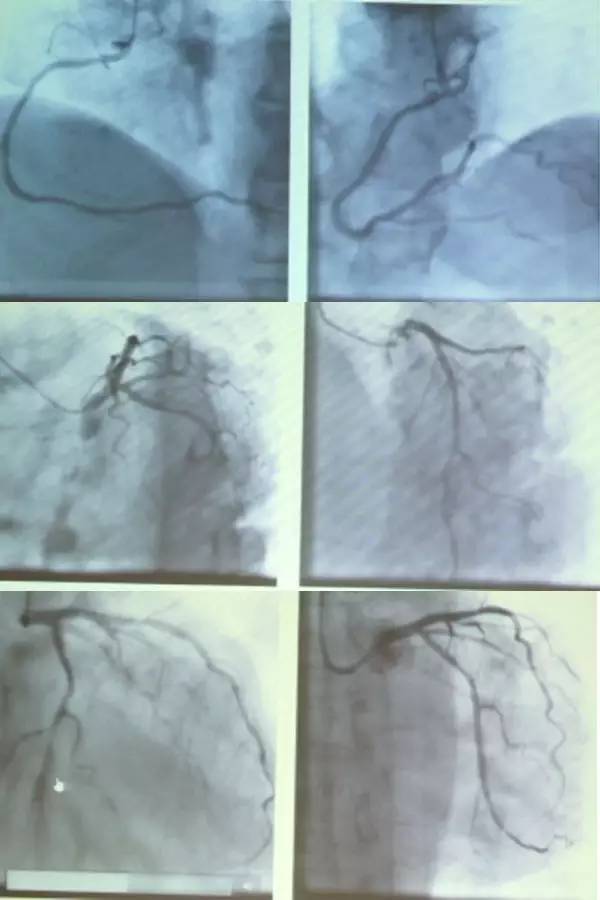

入院后床旁超声心动图(UCG)未见心包积液,三尖瓣中度反流,室间隔搏动减弱,EF值轻度下降,EF 45%。行急诊冠脉造影示,RCA开口畸形,未见明显狭窄,LAD未见明显狭窄,LCX远段弥漫性狭窄95%,前向血流TIMI 2级,于LCX置入1枚支架(图4)。术后患者出现恶心、呕吐、大汗、血压下降。

图4